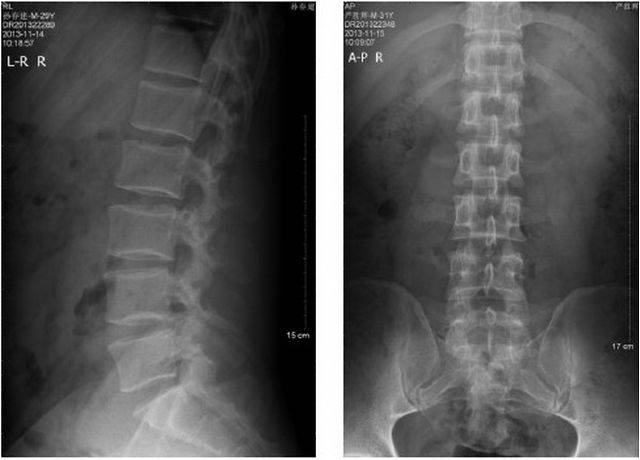

腰椎侧弯图片 x光

腰椎侧弯图片 x光,腰椎侧弯图片x光

腰椎正位: 多显示腰椎侧弯征,椎间隙宽度于病变早期多无改变;如病程

下面这张x光片可以表示脊椎侧弯,从后面看腰椎棘突的连线像写一个「c